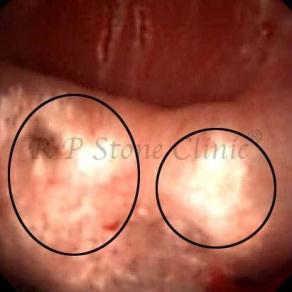

Kidney stone is a solid mass of CRYSTALS. It is the process of crystallization which initiates the formation of kidney stones. This happens in nephrons or units of kidney. Once a small crystal is formed, it can both grow & unite with other crystals leading to the formation of small concretion which eventually forms a stone. Once these large crystals detach from the collecting ducts, the process of stone formation starts in the renal collecting system. A recurrent kidney stone former is advised to know a little bit about something known as Randall’s plaque. Alexander Randall discovered plaques on the renal papillae eight decades back based on examination of 1154 pairs of autopsied Kidneys. He described these renal papillary lesions as cream colored or milk patch areas composed of calcium phosphate & calcium carbonate. These plaques could act as NIDUS for formation of KIDNEY STONE. Calcium Oxalate stone can form on this nidus & then detaches from this plaque to become a free floating stone in the collecting system of kidney

These images are taken as snap shots from the video recording of RIRS Surgery done at our hospital. These are Randall’s Plaques seen with Digital FLEX XC & Digital FLEX XC S. The cream or whitish patches are seen on the tips of RENAL PAPILLAE as seen in images below.